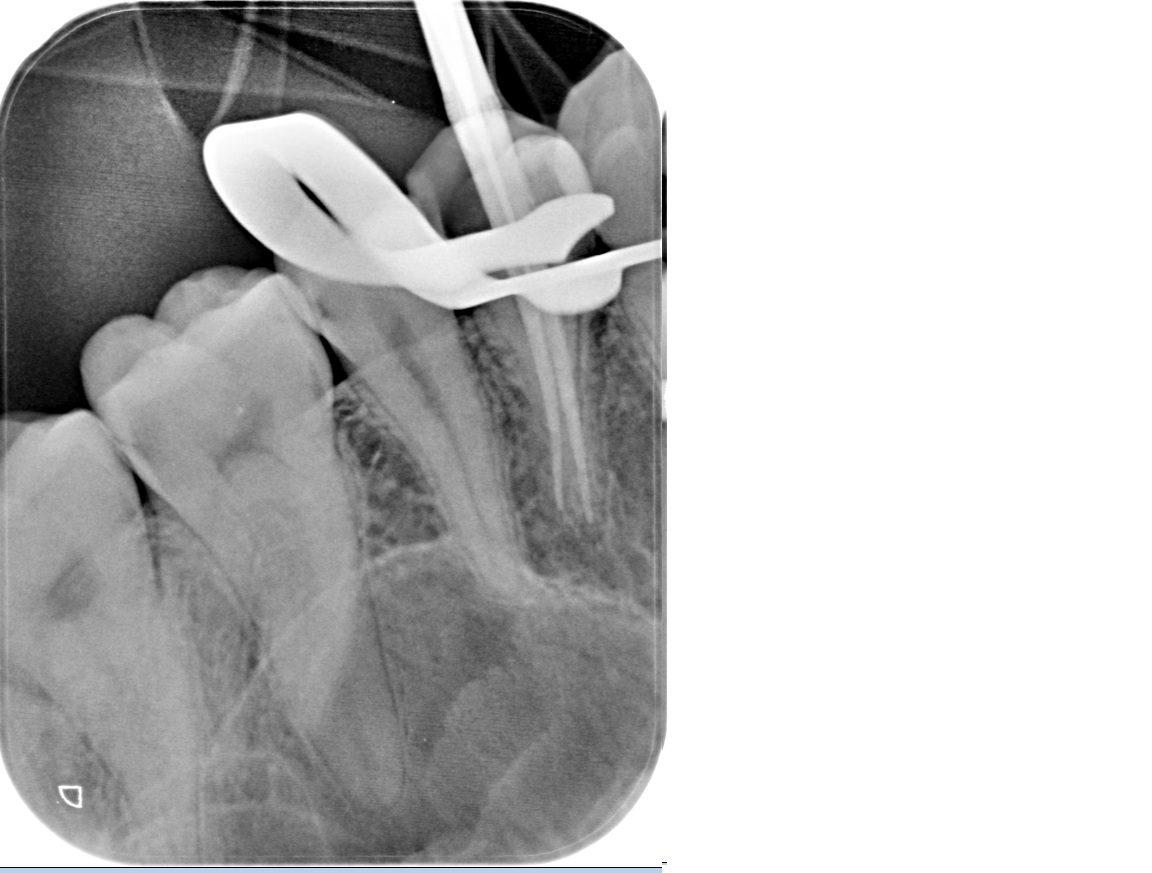

Every procedure is performed under magnification with a rubber dam in place. Electronic length measurement (apex locator) ensures accuracy to the tip of the root. - Thorough cleaning and reliable sealing

We examine the tooth, test its response, and take focused images. When roots are complex or a previous treatment failed, a small 3D scan may be needed for mapping before we discuss and agree on the plan. - Anaesthesia and comfort

Under bright magnified light, a tiny opening is created and every canal located — even the hidden ones that often cause failures elsewhere. - Cleaning and shaping

The canals are shaped with flexible rotary files to create an ideal form for irrigation while preserving tooth strength. - Disinfection